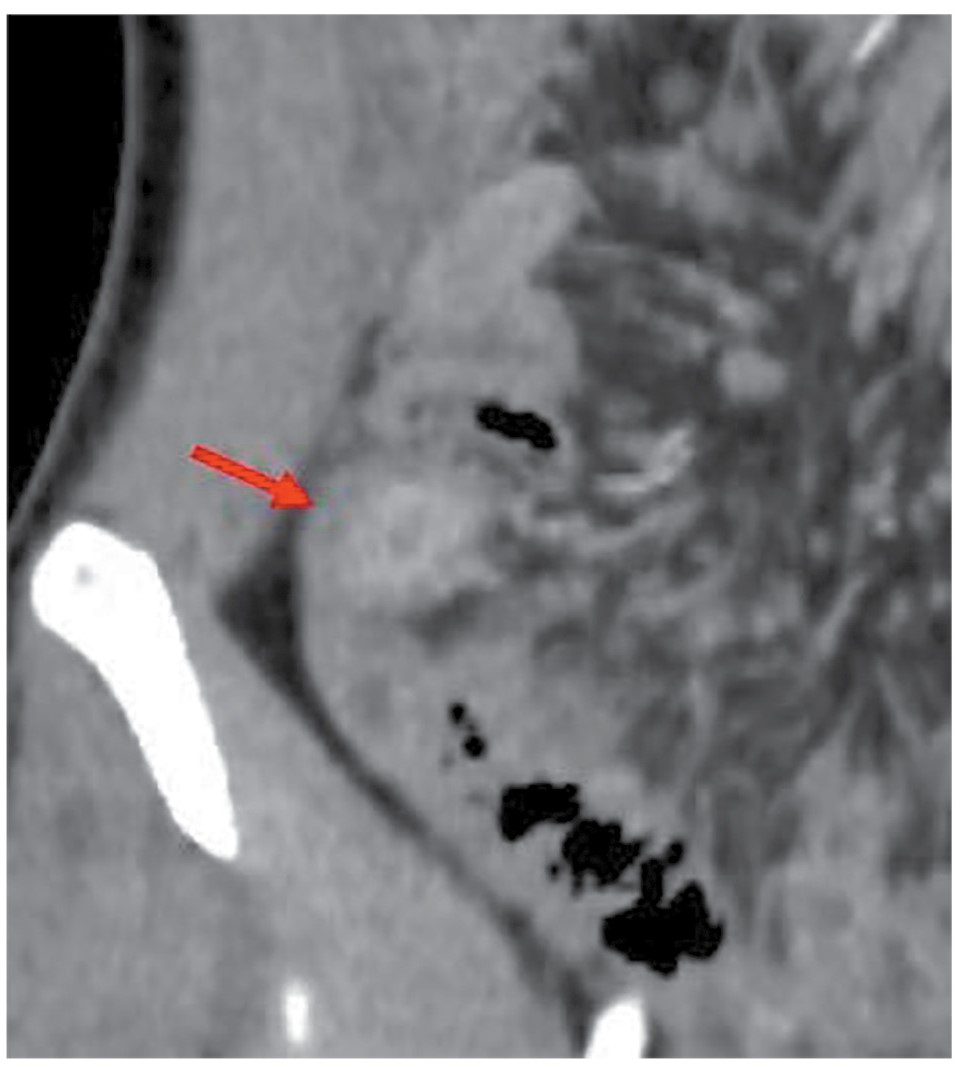

По данным КТ с энтерографией выявлены воспалительные изменения стенок илеостомы (рис. 3), ободочной кишки (рис. 4) и мезентериальная лимфаденопатия (рис. 5).

Рис. 5. КТ-энтерография. Картина мезентериальной лимфаденопатии ободочной кишки.

Fig. 5. CT-enterography. Mesenteric lymphadenopathy of the colon.